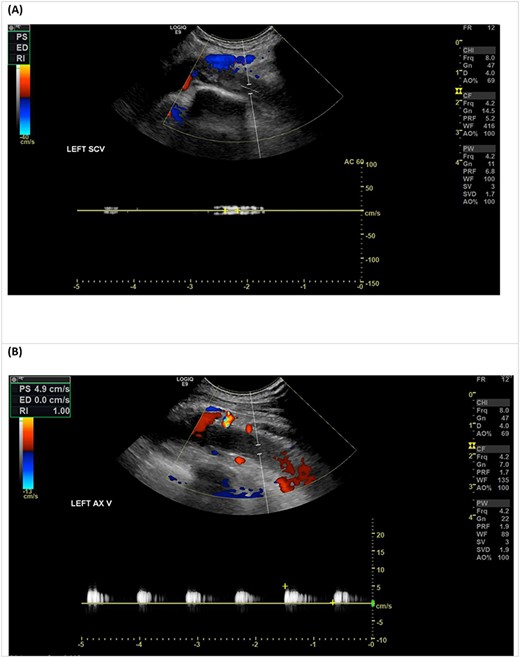

Venous duplex ultrasound of the LUL demonstrating an occlusive thrombus in the left subclavian vein (A), with sluggish flow in the axillary vein (B).

An urgent duplex ultrasound study demonstrated cephalic vein outflow obstruction with occlusive thrombus in the proximal left subclavian/axillary vein confluence (Fig. 1). The basilic vein at the level of the proximal forearm remained patent. He was immediately given a bolus of intravenous unfractionated heparin (UFH) and commenced on a UFH infusion, with a plan for urgent venous thrombectomy.